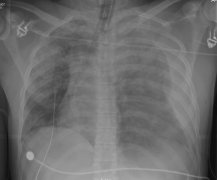

创伤影像关注病人干预的选择,包括腹部损伤、盆腔骨折和主动脉创伤 不同影像方式扮演不同的角色,包括平片,超声(FAST)和CT。 但根据ATLS指南,第一时间关注的是 A. 气道 B. 呼吸 C. 循环 对循环评估的相关影像学包括平片-胸部影像和盆腔影像,以及PAST。...